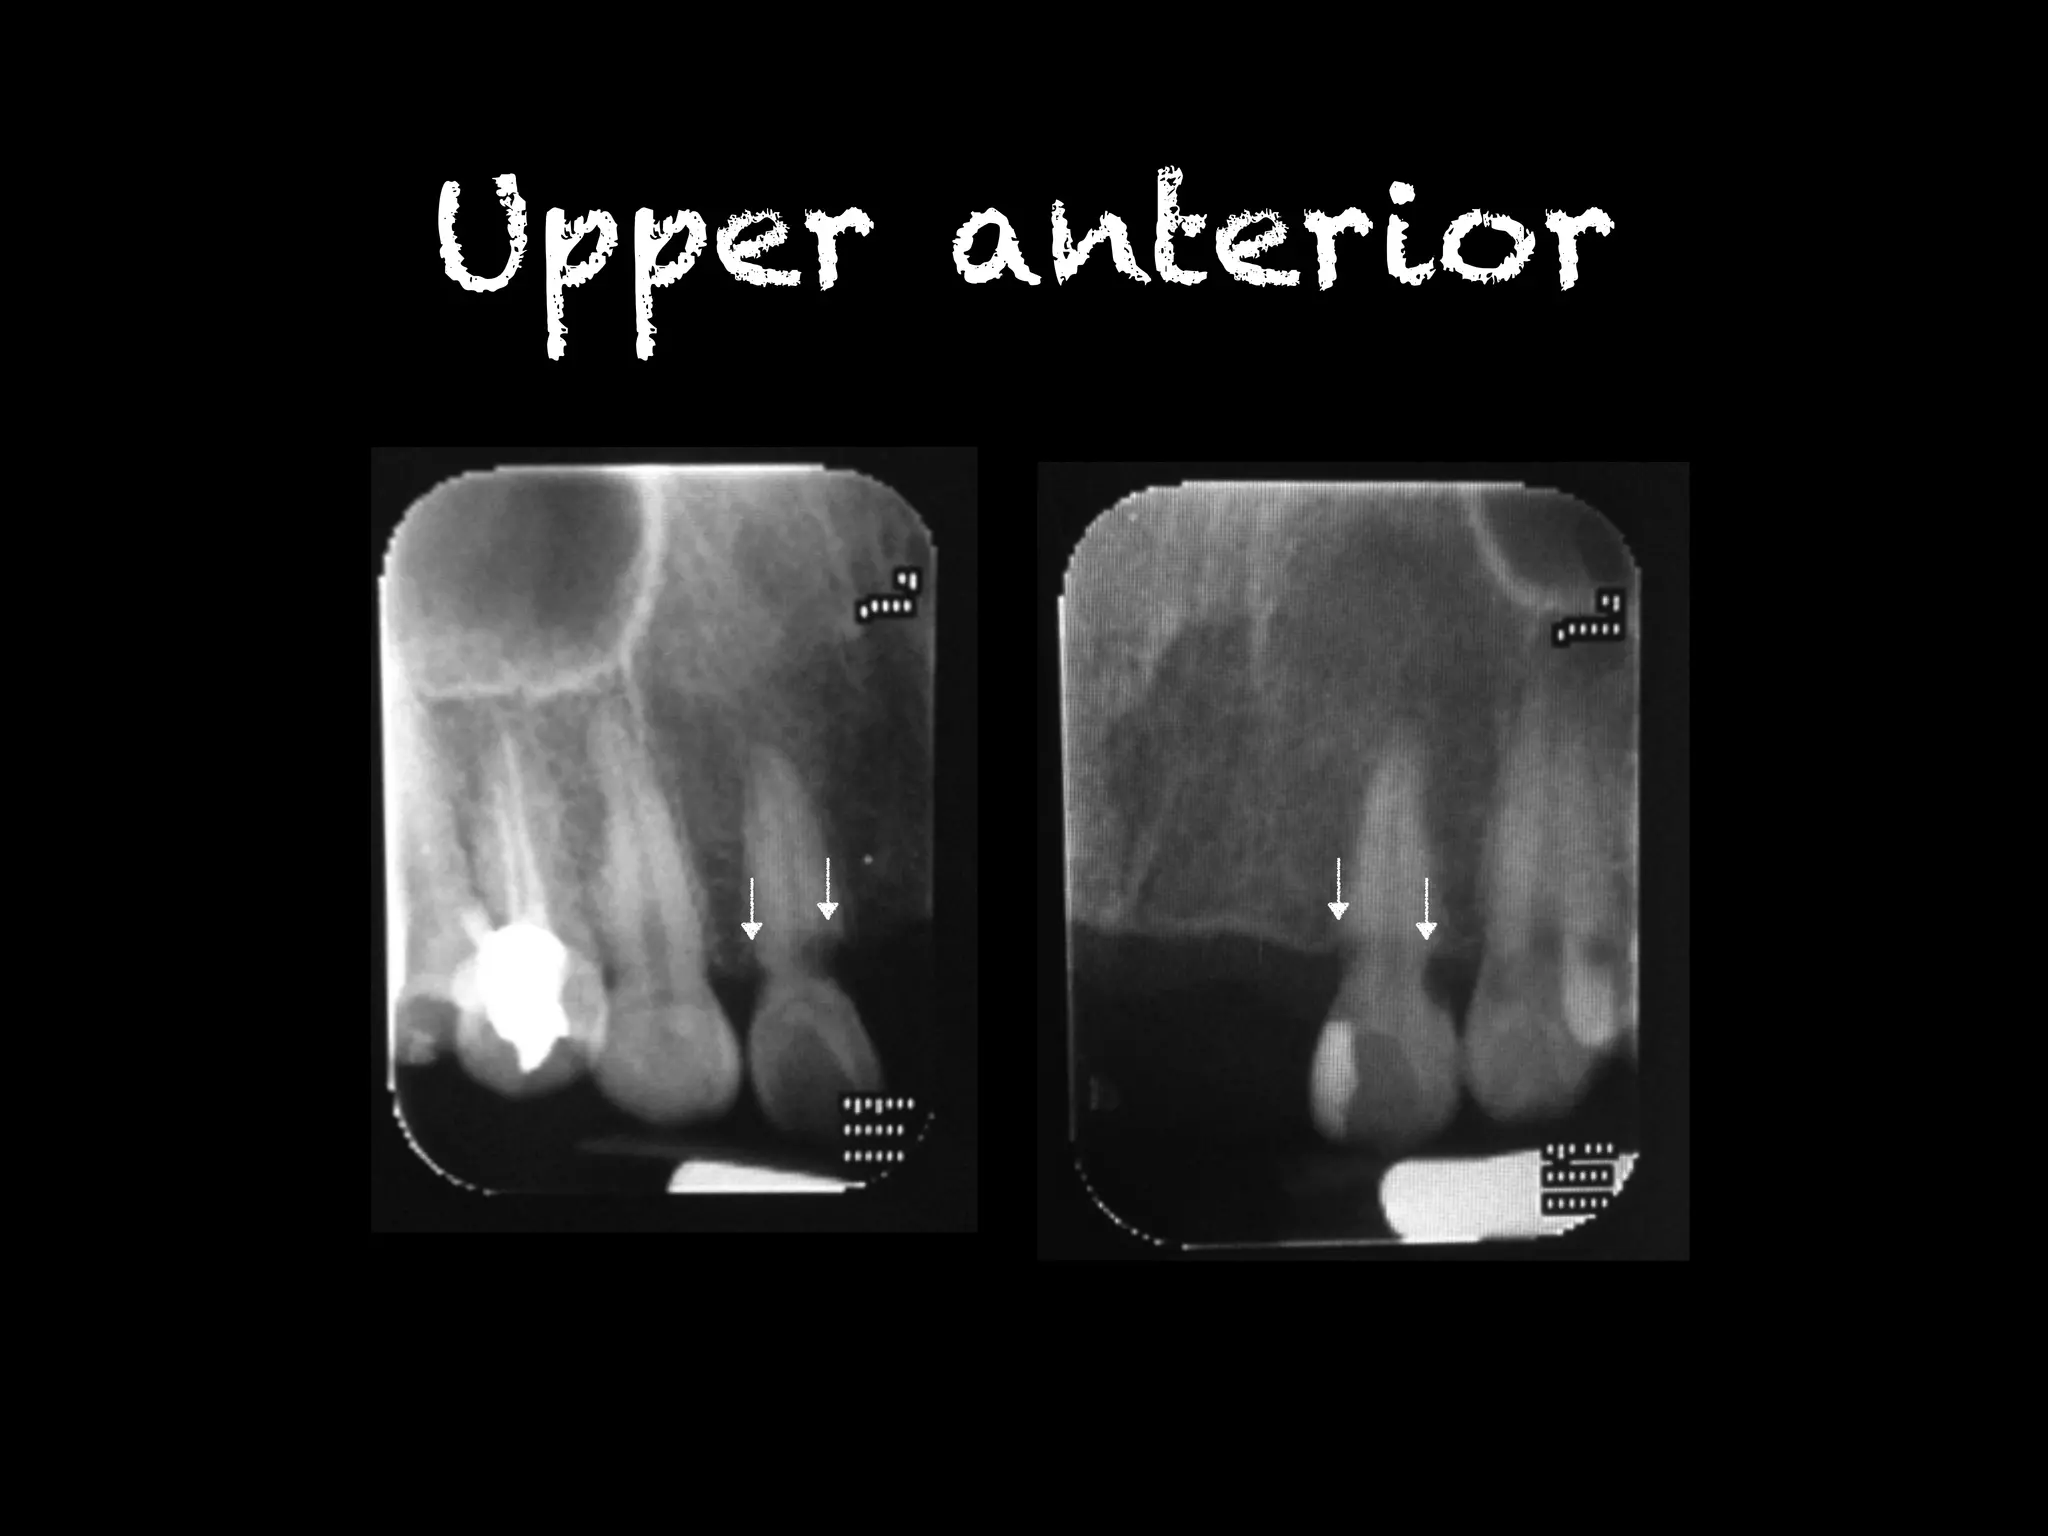

Upper anterior

Upper right

posterior

Upper left posterior

Lower anterior

Radiographic finding พบรอยโรคโปร่งรังสีที่บริเวณคอฟันฟันซี่ 12MD,13M,22MD,23M,31MD,32MD,33MD, 41MD,42MD,43MD,34MD,35MD,36MD, 48M